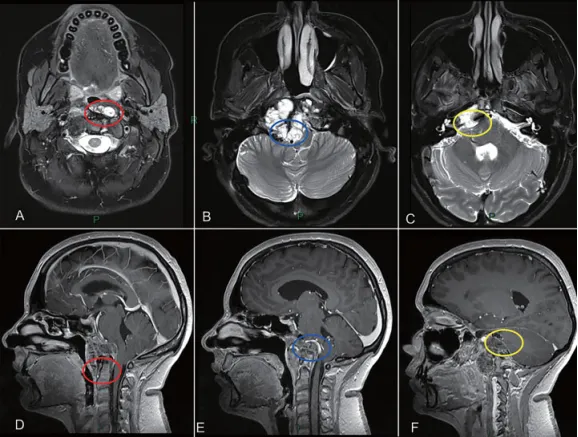

治疗策略分为两个阶段:第一阶段通过经鼻内镜手术切除肿瘤旁正中线区域病灶。存在担忧即使使用可调节角度内窥镜,齿状突旁区域肿瘤底部仍难以触及(图2)。根据MRI影像,怀疑脊索瘤浸润软脑膜平面和后循环血管。

此外,患者有乙状窦后入路手术切除史,预计硬膜内存在广泛组织粘连。右侧枕髁完全被肿瘤侵犯(图1),肿瘤切除后需行颅颈交界区融合术维持稳定。

综上采用两阶段手术方案:第一阶段经鼻内镜切除中线为主肿瘤,第二阶段远外侧入路开颅切除侧方肿瘤,实现最大程度安全切除(图2)。

图2展示颅颈交界区肿瘤手术治疗策略:肿瘤旁正中部分可通过经鼻内镜切除。枢椎齿状突周边肿瘤(A和D红色圆圈)、侵犯硬膜内部分与后循环接触的肿瘤(B和E蓝色圆圈)以及既往乙状窦后入路手术粘连区域(C和F黄色圆圈),这些部位肿瘤更适合第二期远外侧开颅手术。